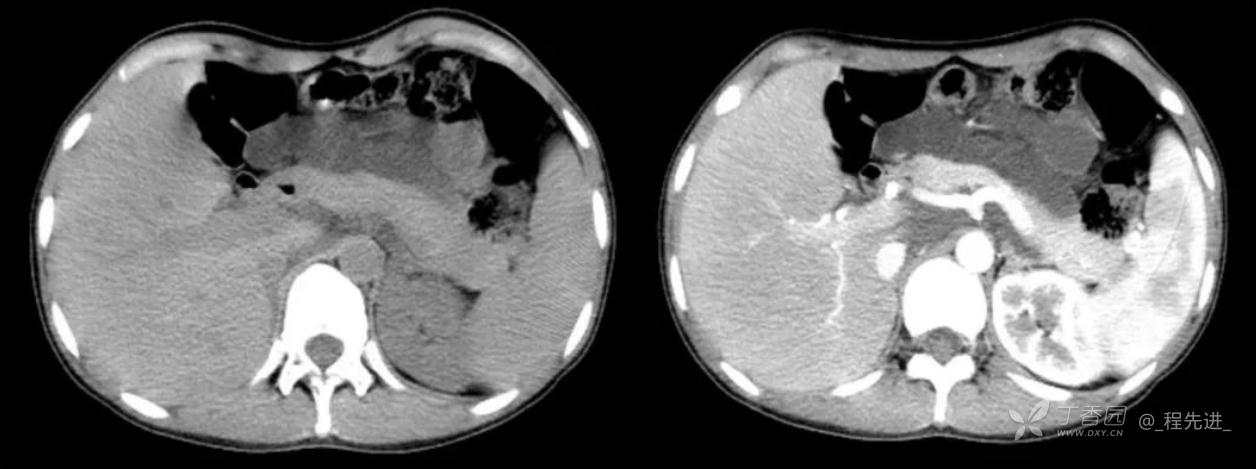

主诉:腹痛、发热一天

现病史:一天前无明显诱因出现腹痛并发热不适,伴恶心、干呕,诊所肌注药物(具体用药不详),无缓解,无明显尿频、尿痛。

体格检查:腹肌稍紧张,右上腹部轻压痛,右肾区叩痛